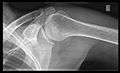

Shoulder imaging

Imaging of the shoulder includes ultrasound, X-ray and MRI, and is guided by the suspected diagnosis and presenting symptoms.

Conventional x-rays and ultrasonography are the primary tools used to confirm a diagnosis of injuries sustained to the rotator cuff. For extended clinical questions, imaging through Magnetic Resonance with or without intraarticular contrast agent is indicated.

Hodler et al. recommend to start scanning with conventional x-rays taken from at least two planes, since this method gives a wide first impression and even has the chance of exposing any frequent shoulder pathologies, i.e. decompensated rotator cuff tears, tendinitis calcarea, dislocations, fractures, usures and/or osteophytes. Furthermore, x-rays are required for the planning of an optimal CT or MR image.[18]

X-ray

These include:

- AP-projection 40° posterior oblique after Grashey

The body has to be rotated about 30 to 45 degrees towards the shoulder to be imaged, and the standing or sitting patient lets the arm hang. This method reveals the joint gap and the vertical alignment towards the socket.[19]

- Transaxillary projection

The arm should be abducted 80 to 100 degrees. This method reveals:[19]

- The horizontal alignment of the humerus head in respect to the socket, and the lateral clavicle in respect to the acromion.

- Lesions of the anterior and posterior socket border or of the tuberculum minus.

- The eventual non-closure of the acromial apophysis.

- The coraco-humeral interval

- Y-projection

The lateral contour of the shoulder should be positioned in front of the film in a way that the longitudinal axis of the scapula continues parallel to the path of the rays. This method reveals:[19]

- The horizontal centralization of the humerus head and socket.

- The osseous margins of the coraco-acromial arch and hence the supraspinatus outlet canal.

- The shape of the acromion

This projection has a low tolerance for errors and accordingly needs proper execution.[19] The Y-projection can be traced back to Wijnblath’s 1933 published cavitas-en-face projection.[20]

CR. shoulay film.

Transaxillary conventional radiography

Y-projection conventional radiography